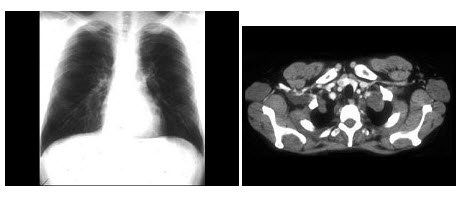

A.胼胝体发育不全

多发性骨髓瘤患者出现咳嗽,咳痰,气急,胸片检查发现病变后行CT检查如图,最可能的诊断为()

A.肺部感染